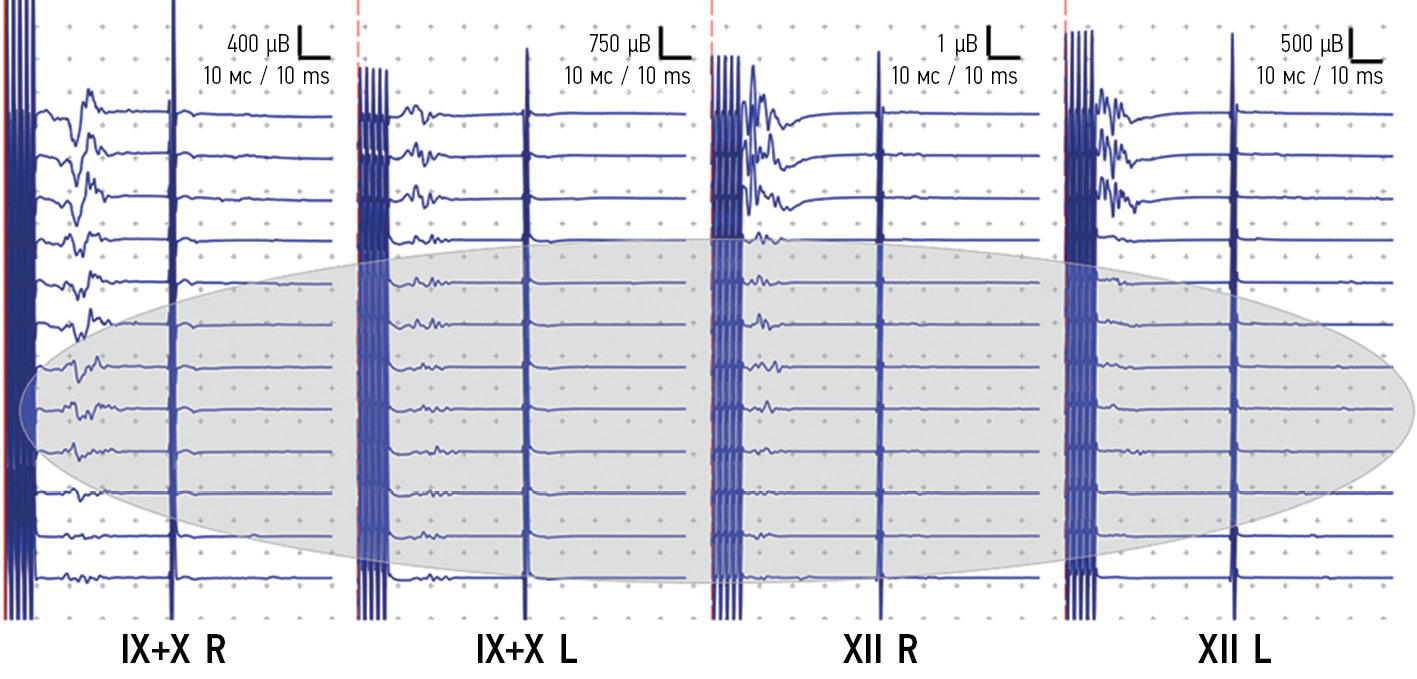

Операцию выполняли в положении пронации на операционном столе под контролем интраоперационного нейрофизиологического мониторинга с использованием модальности КБ-МВП от мышц, иннервируемых подъязычным и языкоглоточным нервами с двух сторон. До начала операции регистрировали стабильные, хорошо воспроизводимые МВП (рис. 3). Была выполнена костнопластическая субокципитальная краниотомия, вскрыта твердая мозговая оболочка. В области отверстия Мажанди обнаружена опухоль серого цвета. Начато удаление опухоли с помощью окончатого пинцета и отсоса. Опухоль мягкой консистенции, гетерогенного строения, с интенсивным кровоснабжением. В толще опухоли располагались крупные опухолевые сосуды, которые интенсивно кровоточили в процессе удаления опухоли. По мере удаления опухоли эти сосуды коагулировали и пересекали. Опухоль распространялась в оба боковых выворота. На периферии опухоль не была отграничена от вещества мозга, грубо инфильтрировала его. Во время удаления части опухоли, которая инфильтрировала дно IV желудочка, отмечали снижение амплитуды КБ-МВП от всех исследуемых мышц на 70–90 % исходного уровня (рис. 3). Учитывая данные ИОМ, а также предположительно злокачественную гистологическую структуру опухоли по данным срочной биопсии, было принято решение данную часть опухоли не удалять. Проведен гемостаз путем коагуляции сосудов и при помощи гемостатической марли. Гистологическое исследование выявило анапластическую эпендимому WHO G III.

Рис. 3. Мониторинг кортикобульбарных моторных вызванных потенциалов от мышц, иннервируемых языкоглоточным, блуждающим, подъязычным нервами билатерально. При удалении опухоли в области писчего пера отмечается снижение амплитуды моторного вызванного потенциала от всех исследуемых мышц

Fig. 3. In the figure, motor evoked potentials of cranial nerve IX, X, XII are being recorded. Indication shows reduction of MEPs during removal of a tumor in the area of calamus scriptorius